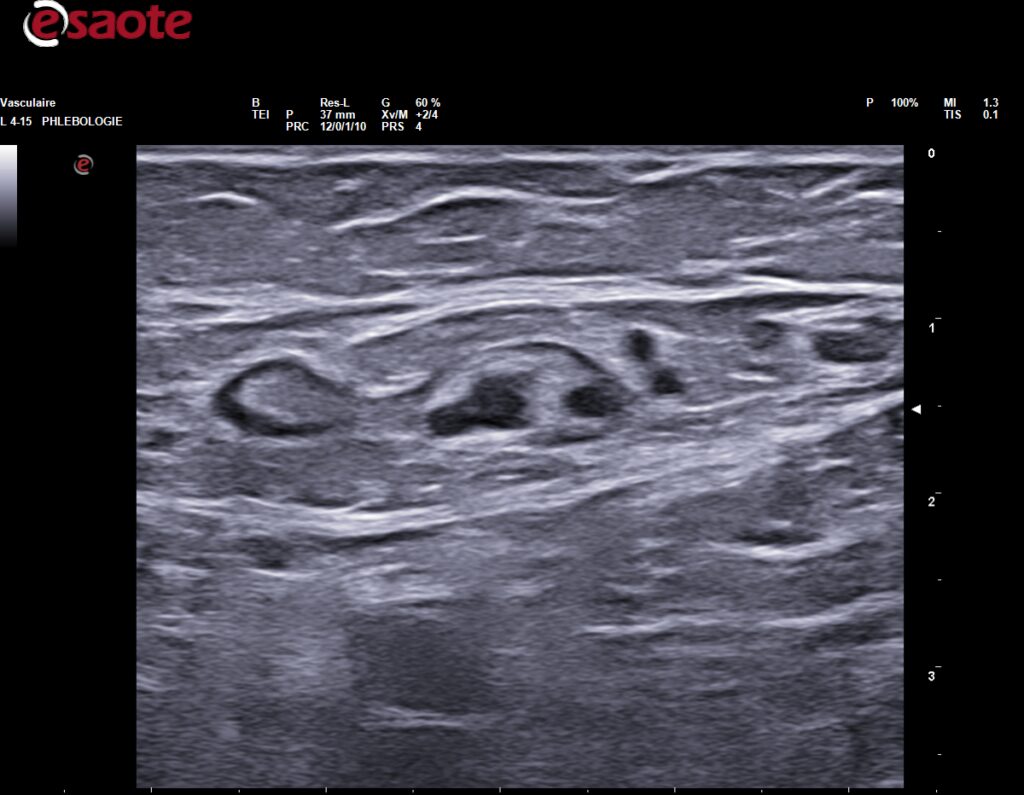

Une étude approfondie du réseau veineux, au niveau du tiers supérieur de la cuisse, par bilan échoDoppler, est nécessaire avant l’injection de mousse sclérosante afin d’éviter une injection intra-artériolaire (photo 1 lame lympho-ganglionnaire inguinale avant injection, photo 2 présence d’une artériole à proximité de la veine incontinente).